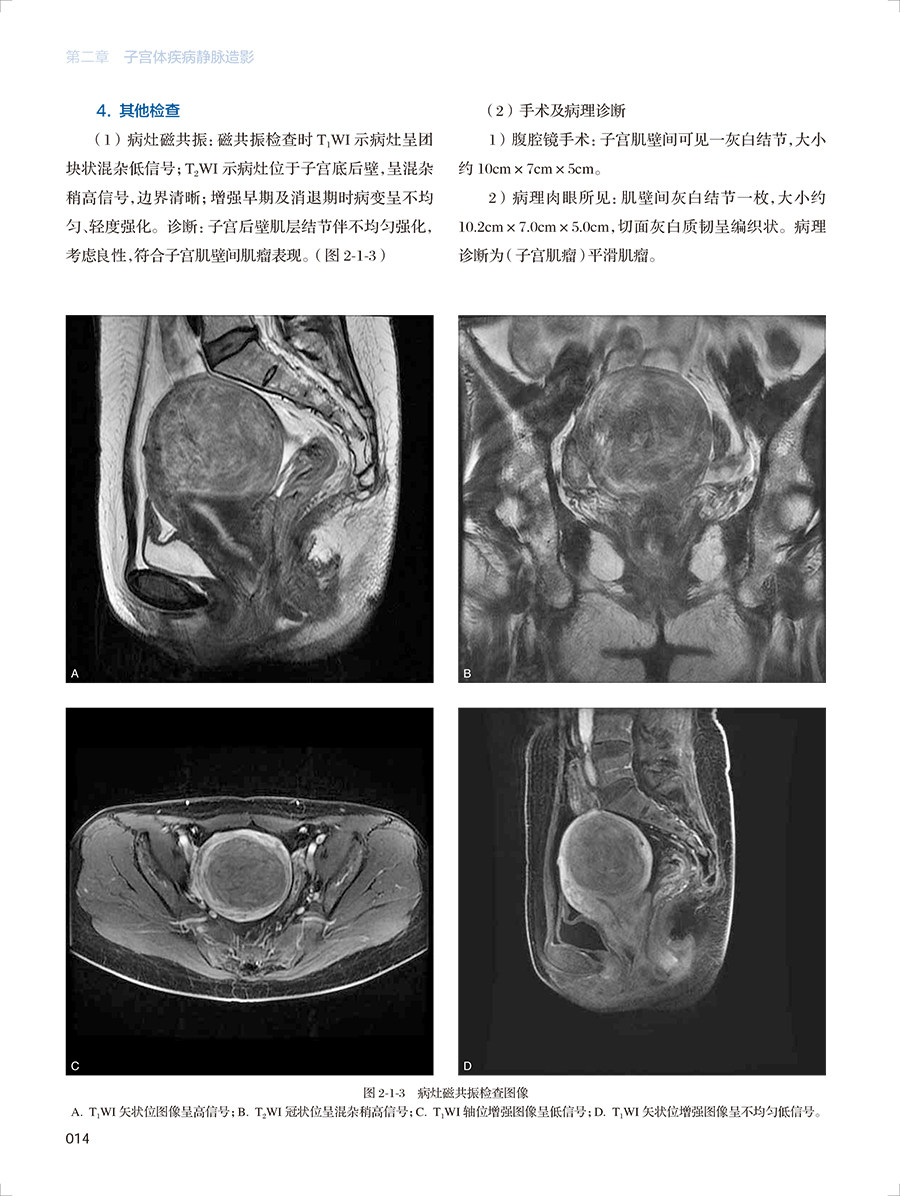

第二章子宫体疾病静脉造影

第一节子宫肌瘤

一、肌壁间肌瘤

六、恶性潜能未定的平滑肌肿瘤